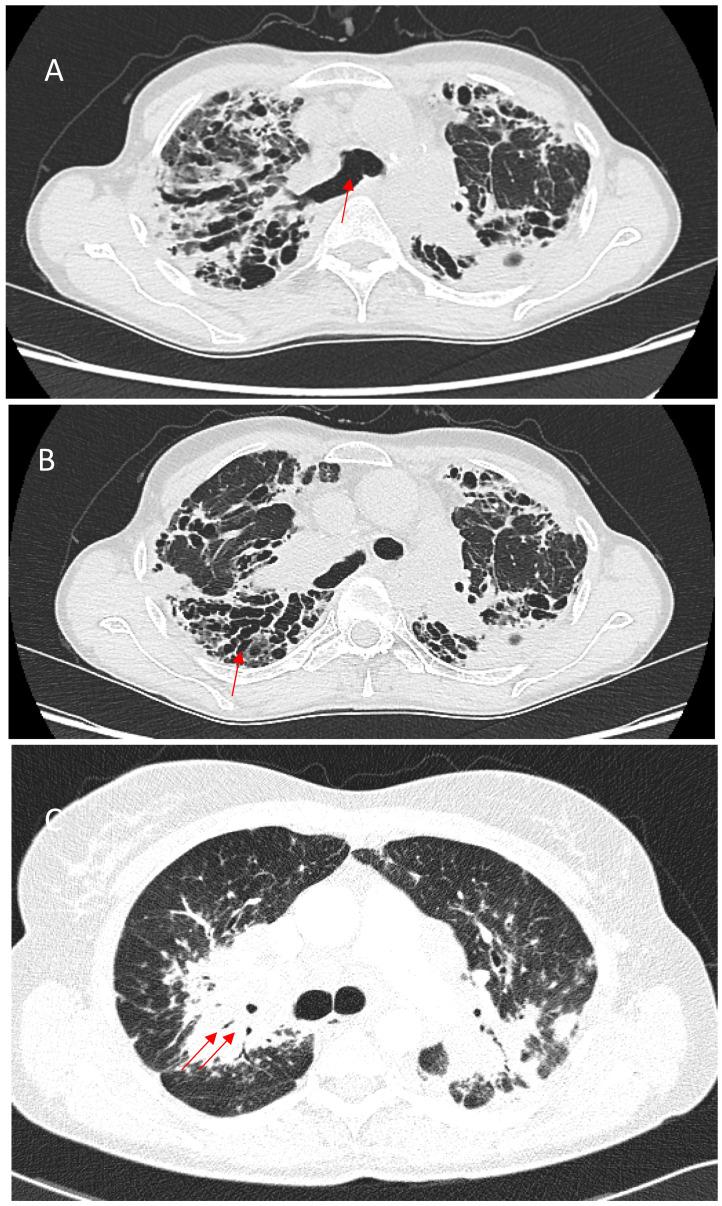

Sarcoidosis is a multiorgan, granulomatous disease of an unknown etiology. The characteristic feature of the disease is the formation of noncaseating granulomas. Spontaneous resolution occurs in most patients, but the clinical course may be chronic or progressive, complicated by pulmonary fibrosis, which is a major cause of mortality in sarcoidosis. Recent studies have provided new information on the immunological mechanisms of pulmonary fibrosis. Its pathogenesis includes the alteration of lymphocyte activity and the imbalance between their subpopulations, the polarization of macrophages to the profibrotic phenotype, and an imbalance between the activity of metalloproteinases and their tissue inhibitors. A multidisciplinary approach is required for the optimal management of fibrotic pulmonary sarcoidosis. Clinical symptoms, serum biomarkers, imaging, pulmonary function test results, other organ involvement, comorbidities, and complications should be considered when assessing disease activity and selecting the most appropriate treatment. The use of anti-inflammatory drugs is often discussed. There has been no consensus reached on whether antifibrotic agents should be added or used in monotherapy as initial treatment in such cases. This article will review all the information on fibrotic pulmonary sarcoidosis and present factors associated with fibrosis development, prognosis, and treatment options.

结节病是一种病因不明的多器官肉芽肿性疾病。该病的特征性表现是形成非干酪样肉芽肿。大多数患者可自发缓解,但临床病程可能是慢性或进行性的,并伴有肺纤维化,这是结节病患者死亡的主要原因。最近的研究提供了关于肺纤维化免疫机制的新信息。其发病机制包括淋巴细胞活性改变及其亚群之间的失衡、巨噬细胞向促纤维化表型的极化,以及金属蛋白酶与其组织抑制剂活性之间的失衡。对于纤维化型肺结节病的最佳管理需要多学科方法。在评估疾病活动度和选择最合适的治疗方法时,应考虑临床症状、血清生物标志物、影像学检查、肺功能测试结果、其他器官受累情况、合并症及并发症。抗炎药物的使用经常被讨论。对于在这类病例中是否应添加抗纤维化药物或使用其单一疗法作为初始治疗,尚未达成共识。本文将综述关于纤维化型肺结节病的所有信息,并介绍与纤维化发展、预后及治疗选择相关的因素。